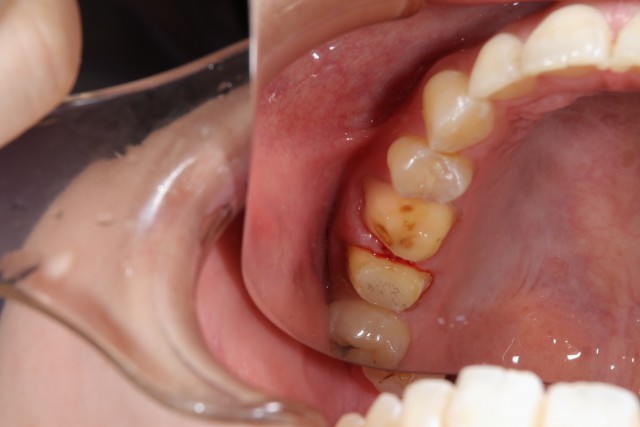

施術中

金属で治療してあったものをはずし土台を形成しなおします。このように自分の歯を土台として使える場合にはそのまま型を取りかぶせるクラウンという施術方法で治療していきます。また、今回のようなメタルフリーの場合黒ずみなどもなくキレイに仕上げることが出来るのもメタルフリーの特徴の一つです。